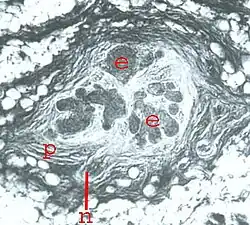

Im histologischen Bild zeigen sich zahlreiche Epithelknospen, eingebettet in zell- und nervenreiches Bindegewebe. Am Epithel enden an vielen Stellen sensorische Nervenästchen. Es gibt aber auch viele spezialisierte Nervenendkörperchen.